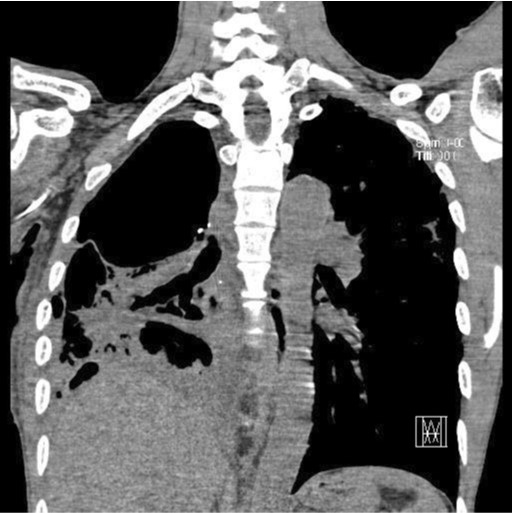

Fig. 1.

Chest radiograph after right upper lobectomy show deadspace of right thoracic cavity and multifocal consolidation at right lower lobe.